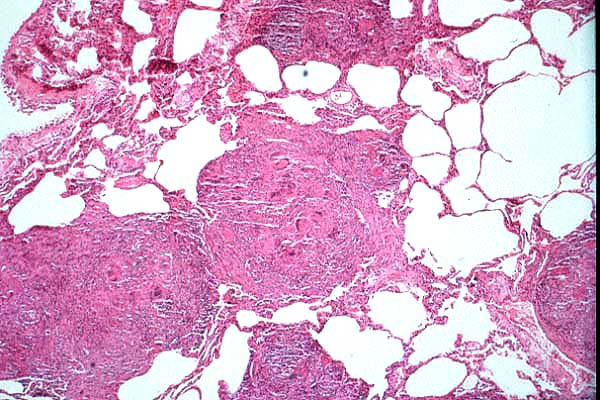

e

(H&E)

- Case 23-1. Multifocally within the lung, there are

fibrotic foci (e,f) that contain neutrophils (f,g), epithelioid

cells (f,g), occasional foreign body giant cells (e,f,g), and

scattered 8-12u diameter yeast bodies (f,g).